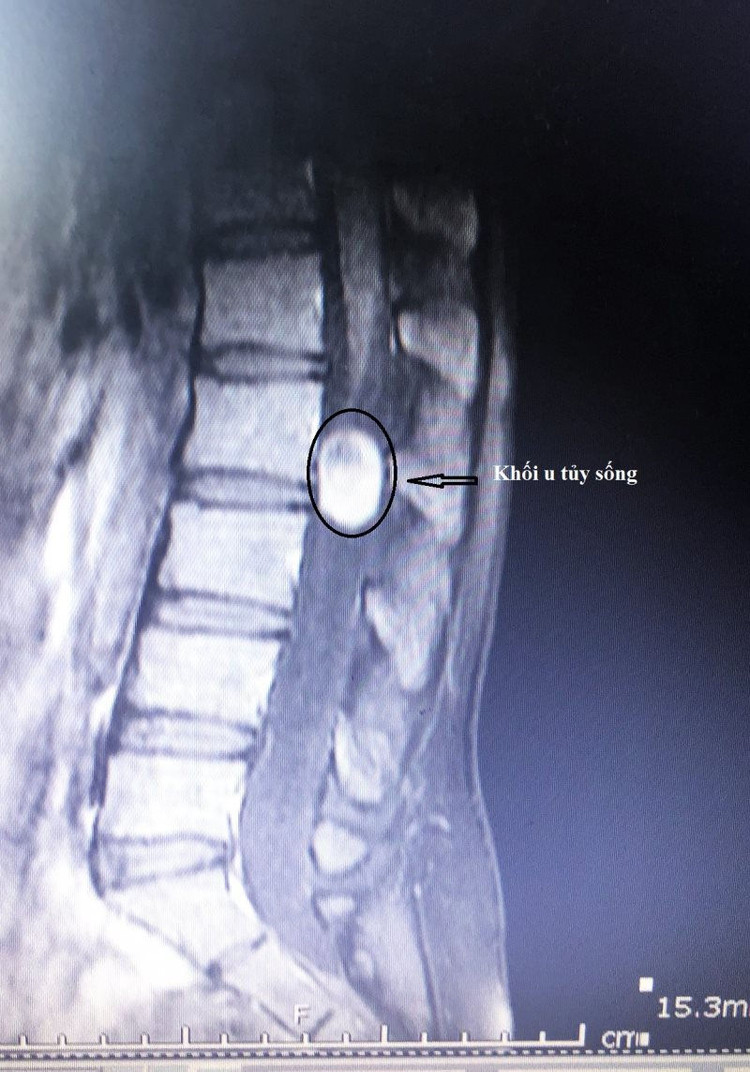

Bệnh nhân N.T.B. (24 tuổi, Quảng Ninh) bị cứng đau lưng nhiều, tê bì tay chân, đi lại khó khăn... nghĩ là bệnh do đau xương khớp nên tự điều trị bằng các phương pháp Đông y, nhưng không cải thiện. Tại Bệnh viện Bãi Cháy, kết quả chụp cộng hưởng từ cho thấy hình ảnh khối u tủy sống kích thước lớn chiếm chọn ống sống gây nên hội chứng chùm đuôi ngựa (CES – tình trạng các rễ của đám rối thần kinh đuôi ngựa bị chèn ép, làm ảnh hưởng đến chức năng vận động, cảm giác, đến hai chi dưới và bàng quang, trực tràng). Bệnh nhân được chỉ định phẫu thuật vi phẫu lấy khối u, giải phóng chèn ép lên ống tủy.

vi-phau-tuy-song-4.jpg

Khối u tủy sống chiếm chọn ống sống.